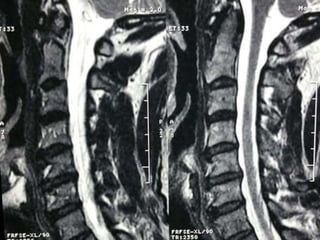

48 year old man with right fifth finger pain and numbess

S/P C7T1

ACDF

persistent

symptoms of

ataxia, neck

pain, fine

motor hand

dysfunction

48 year oldman with right fifth finger pain and numbess

persistent symptoms of ataxia, neck pain,fine motor hand dysfunction